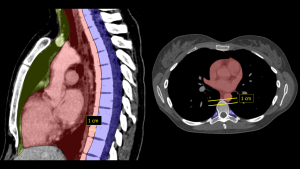

To address localization inconsistencies, the International Thymic Malignancy Interest Group (ITMIG) established a standard CT-based classification (2017), dividing the mediastinum into three distinct compartments [1]. This anatomical division provides a systematic framework for differential diagnosis based on the specific contents of each zone:

- Prevascular Compartment:

- Definition: From the posterior border of the sternum to the anterior aspect of the pericardium.

- Contents: Thymus, fat, lymph nodes, and the left brachiocephalic vein.

- Visceral Compartment:

- Definition: Extending from the posterior boundary of the prevascular zone to a vertical line 1 cm posterior to the anterior margin of the thoracic vertebral bodies.

- Contents: Vascular structures (heart, aorta, SVC, pulmonary arteries), thoracic duct, and non-vascular organs (trachea, esophagus, lymph nodes).

- Paravertebral Compartment:

- Definition: The posterior-most region, extending laterally to the transverse processes.

- Contents: Thoracic spine, paravertebral soft tissues, and neural elements.

Fig 1: CT Visualization of Mediastinal Compartments (Based on ITMIG 2017 classification [1]). Sagittal overlay (Left) delineates the three distinct zones: Prevascular (yellow), Visceral (red), and Paravertebral (blue). Axial view (Right) demonstrates the Visceral (red) and Paravertebral (blue) compartments. Note that the prevascular compartment is not visible at this specific anatomical level.